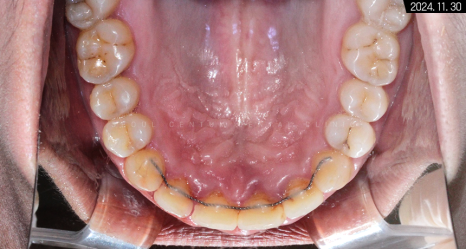

치아 교정을 바르게 마쳐서 그런지

구강을 상하측에서 봤을 때도

이전보다 가지런해진 치열이 보입니다.

중절치 중심선도 일치하고

앞니끼리 톱니바퀴처럼 견고하게 맞물려있고요.

이처럼 구치부부터 전치부까지

어느 하나 비틀어진 곳 없이

바르게 맞물리게 되었습니다.

악궁과 U자 모양도

부드러운 곡선을 갖추고 있죠.

적절히 둥근 모양이 참 보기 좋습니다.

어금니 수평 관계도 좋고 정출된 곳 없이

정상 라인 안에 치아가 모두

들어온 것을 확인할 수 있습니다.